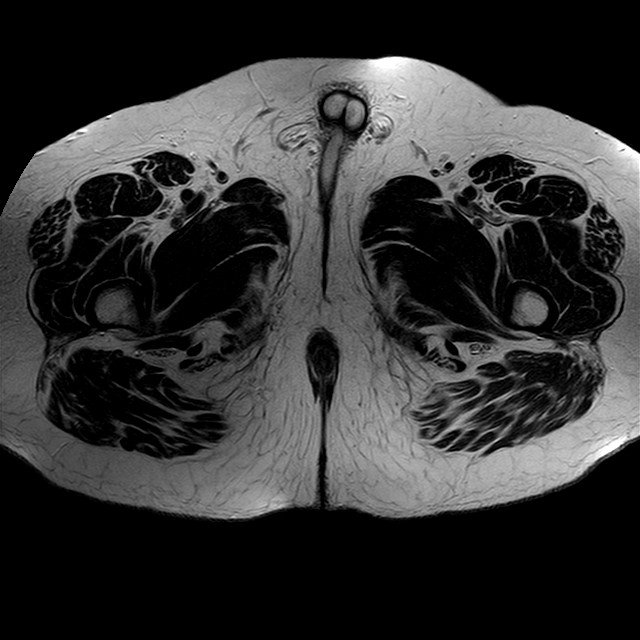

Esami: RMN BACINO

eT2w TSE

Evidenti e simmetriche alterazioni osteofitosiche in regione coxo femorale con riduzione delle rime articolari. Degenerazione completa del cercine glenoideo. Non attuali segni di versamento articolare. Non segni di edema osseo che escludono attuale algodistrofia od osteonecrosi. Lieve e simmetrica riduzione del trofismo della muscolatura glutea.